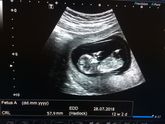

Увидела в ленте пост про количество детей и нормы, сколько у детей и прочее. У моей прабабки по маминой линии 4 детей, а у бабушки по папиной 6 , у всех дядек и теток по 3 ребенка минимум- лично я хочу ограничиться одним пупсом, вроде не свиноматка и … Читать далее